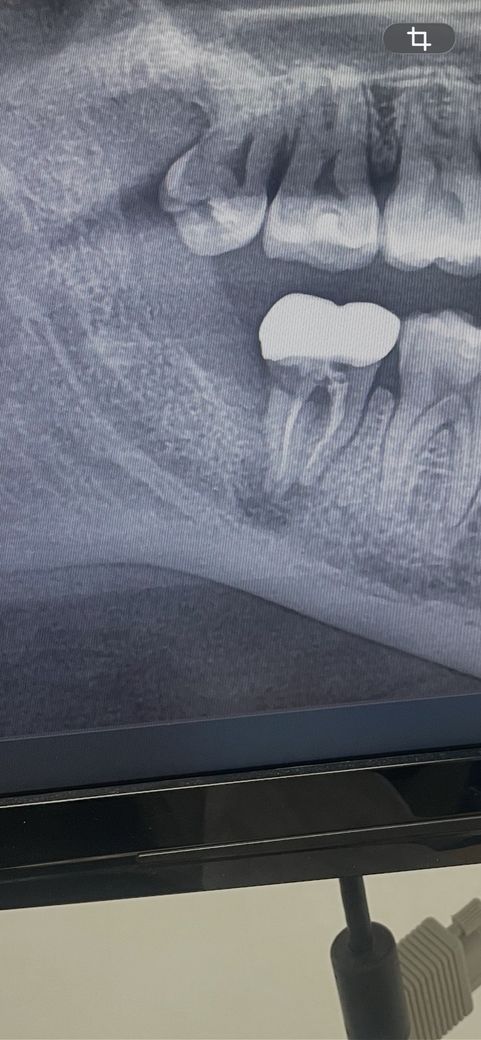

어제 밤부터 예전에 신경치료하고 크라운씌운 곳이 아파서 오늘 병원에 가니까 재신경치료 안된다고 무조건 발치 후 뼈이식 한 후에 임플란트 해야한다는데 다른 방법이 없나요 정말로

애초에 신경치료 난이도가 높은 치아입니다. 처음 한 신경치료의 퀄리티가 나쁘지 않음에도 불구하고 이렇게 염증이 다시 잡힌 경우 재신경치료를 해도 증상이 아주 드라마틱하게 호전될 가능성이 높진 않습니다. 물론 시도해볼 순 있습니다. 재신경치료나 치근단 절제술 등의 방법은 있으나 너무 기대하진 마시기 바랍니다.

재신경치료가 불가능한 것은 아니나 재신경치료로 인하여 다시 살릴 가능성이 크지 않습니다. 또한 재신경치료를 하기에 앞서 염증이 신경과 가깝거나 이미 닿이 있으므로 재신경치료 자체가 굉장히 어려울 수 있습니다. 지금 상태에서는 재신경치료도 맞는 치료지만 치아를 뽑고 임플란트를 해야할 정도로 치아가 안 좋은 것도 사실입니다. 만약에 재신경치료를 원한다면 대학병원 방문 후 현미경 하에서 진행해야할 가능성이 매우 높습니다.

보존과 전문의에게 진료 한번 받아보시는것이 좋아보이며 골소실량이 큰 편이라서 재신경치료 진행하더라도 예후 불량하리라 사료됩니다. 더불어 하치조신경관과 치근단 병소 인접해있어 이와관련된 사항도 충분히 고려해서 치료 받으셔야합니다.